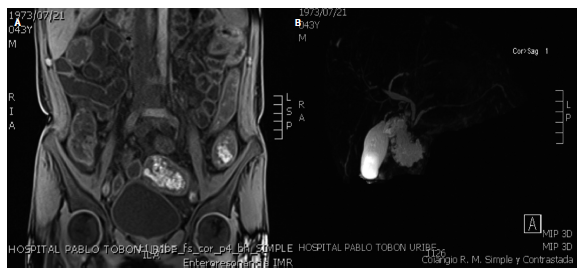

Se realizaron estudios endoscópicos en nuestra institución y se observaron lesiones que recuerdan pseudodivertículos (como en sacabocados) en el esófago distal (Figura 1A); mucosa gástrica de aspecto granular, apariencia de empedrado, principalmente en el cuerpo distal y el antro, con una úlcera inflamatoria en la región pilórica (Figura 1B) y formaciones pseudodiverticulares de aspecto inflamatorio crónico en el duodeno (Figura 1 C). La colonoscopia mostró una mucosa con una grave inflamación de todo el colon, con estenosis inflamatoria en la válvula ileocecal y múltiples úlceras inflamatorias en el íleon distal (Figura 1D-F). Se solicitó una enterorresonancia (entero-RMN) en la que se evidenció compromiso extenso de todo el intestino delgado por engrosamiento difuso, concéntrico, asimétrico e irregular desde el estómago hasta el recto (Figura 2A). Por la elevación de FA y GGT se realizó una colangio-RMN en la que se encontraron segmentos estenóticos lisos y cortos que alternan con segmentos de mayor calibre en la vía biliar intrahepática derecha e izquierda asociado con realce difuso de las paredes por un fenómeno inflamatorio inespecífico (Figura 2B). Las biopsias colónicas mostraron una mucosa ulcerada con distorsión de criptas, disminución de células caliciformes, infiltrado linfoplasmocitario en la lámina propia, exocitosis de polimorfonucleares y formación de microabscesos, Con tinción ZN, tinción ZN modificada, tinción de PAS (periodic Acid-Schiff) y citomegalovirus (CMV) negativos.